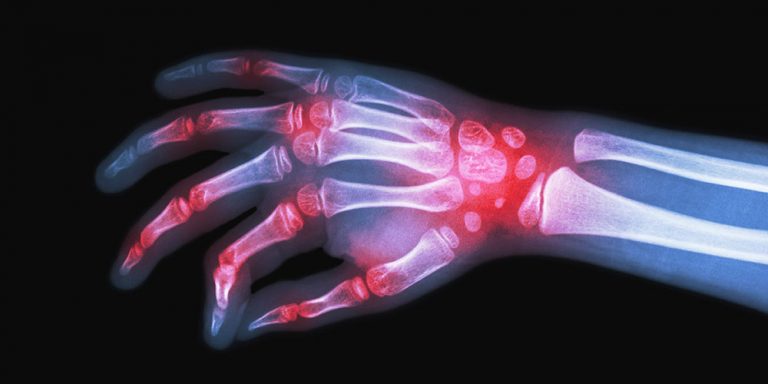

Conteúdos educativos e orientações sobre doenças reumáticas.

Cartilhas para pacientes

Arterite de Takayasu

Doença inflamatória crônica que pode afetar várias articulações e com causa ainda desconhecida

Artrite Idiopática Juvenil

Doença inflamatória crônica que acomete as articulações e outros órgãos, como a pele, os olhos e o coração